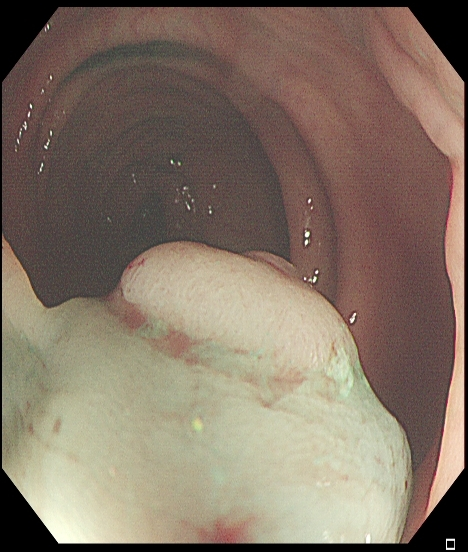

对于大型Ⅰp病变,除以上注意事项外,应采用热圈套方式切除,切除前应于蒂根部充分黏膜下注射(经内镜注射针将2~10 mLl万单位的肾上腺素+亚甲蓝+生理盐水混合液注射于黏膜下,边退针边注射),致使蒂部充分隆起,易于切除(图 3),切除过程中病变应避免接触肠壁,以免形成闭合回路,灼伤肠壁。

需要注意的是大型Ⅰp型息肉若蒂部较粗,则可能含粗大滋养血管,切除后极易出血。切除过程中可采用凝-切-凝的方式,减少出血风险。部分较大息肉,可采取分块切除方式,降低操作难度,但此法不利于病理评估。